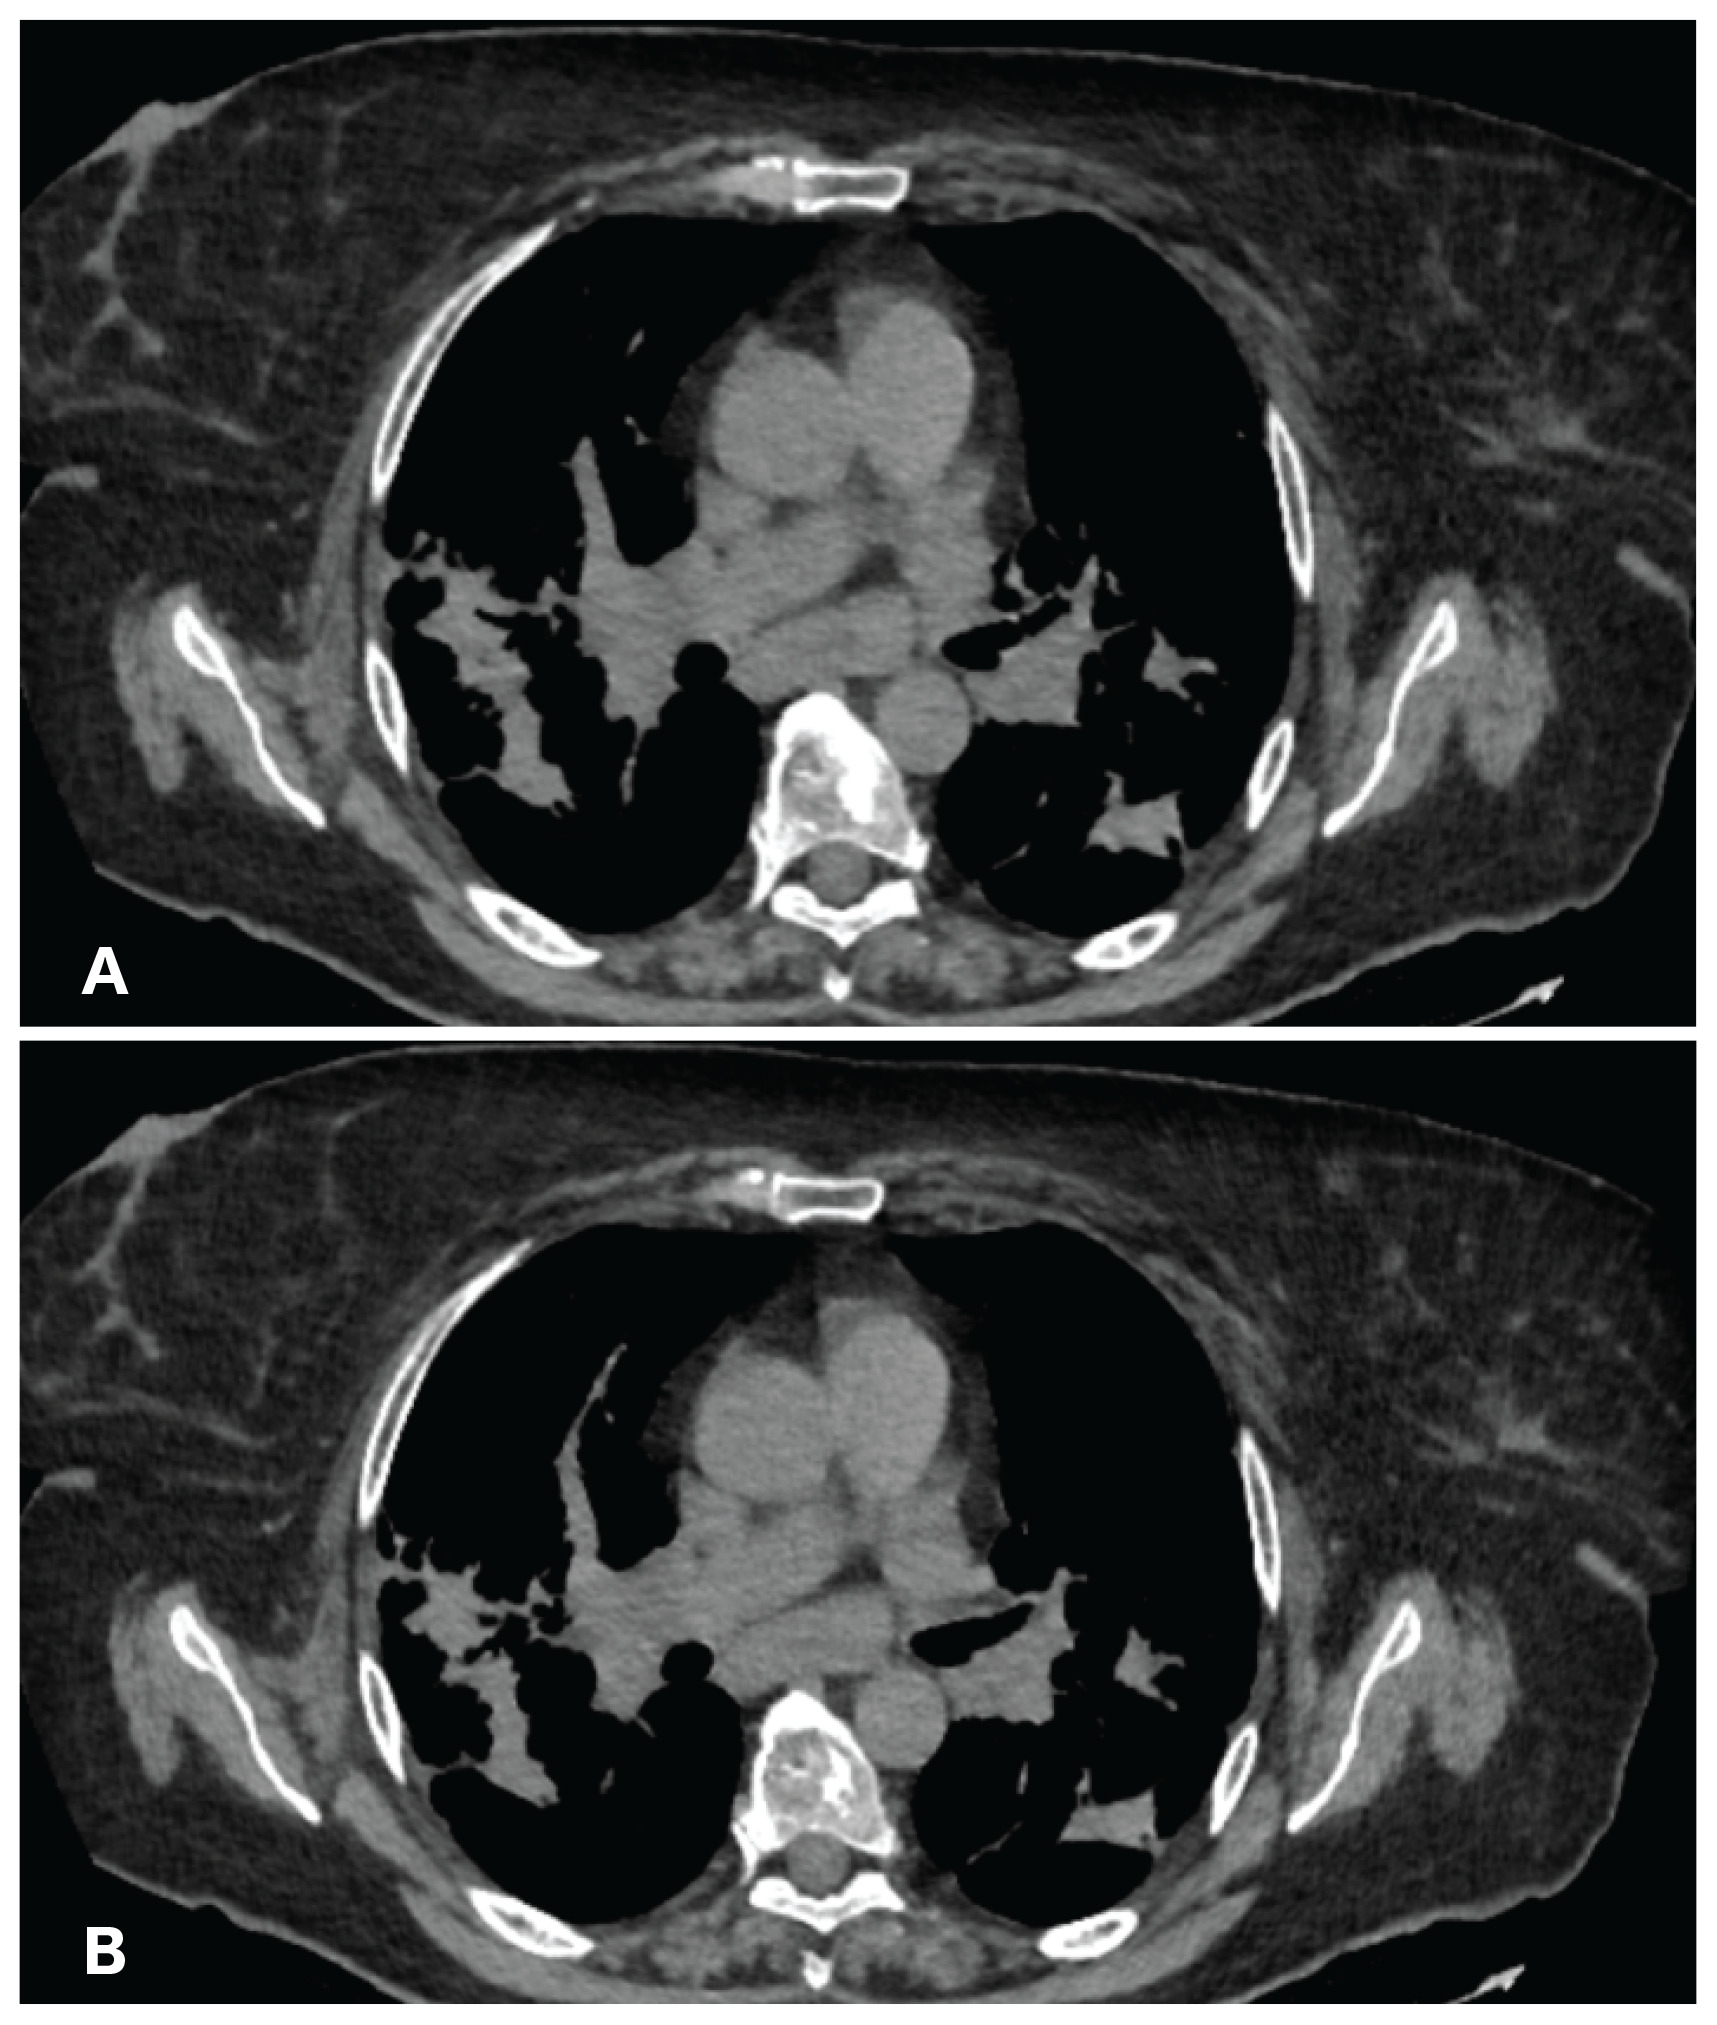

A 65-year-old female of German origin, current smoker, without occupational exposure to inhaled substances, was referred to our institution with fatigue, thoracic pain in the interscapular area and joint pain for the past 3 months. Her past medical history included diabetes mellitus type II with symptoms of diabetic neuralgia and dyslipidemia, for which she was treated with insulin glargine, sitagliptin, gabapentin and tramadol/acetaminophen. During the past three months the patient underwent a series of medical examinations, one of which was chest CT as part of the investigation for her fatigue and chest pain. High resolution chest computed tomography (HRCT) revealed mediastinal lymphadenopathy in stations 2, 3, 4, 5, 7 and 10 (Figure 1), along with bilateral patchy infiltrates in the pulmonary parenchyma (Figure 2).

Figure 1

A) and B): Patient’s chest CT showing the enlarged upper paratracheal lymph nodes (LN 2L) and right lower paratracheal (LN 4R)